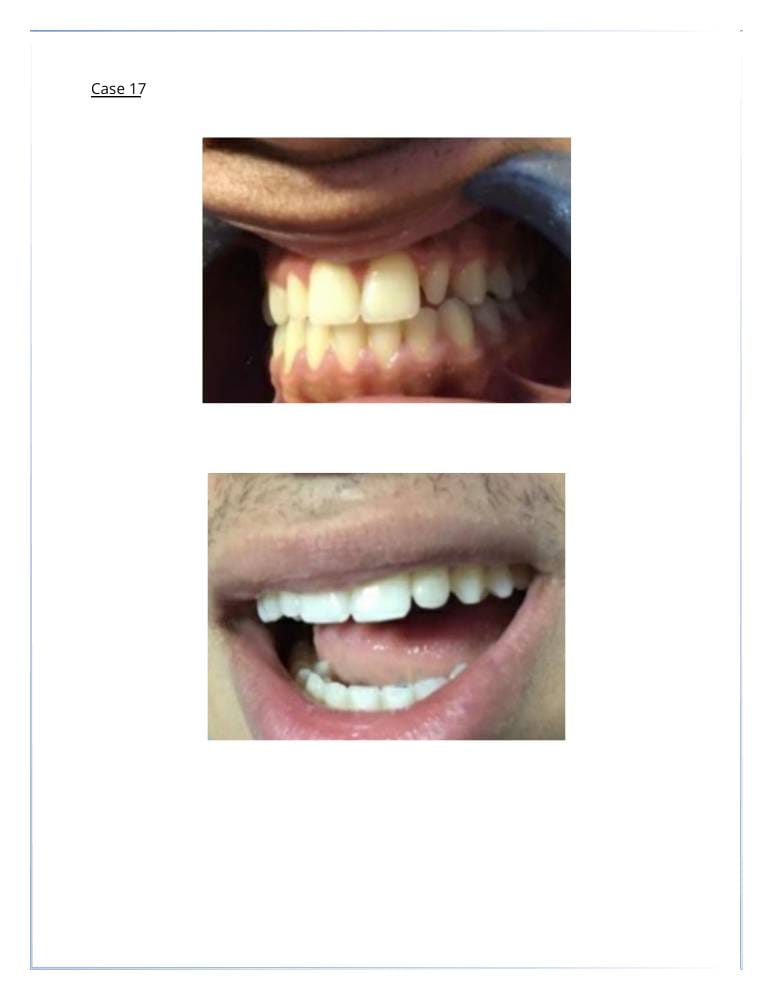

التجميل السني

- اكدت الدراسات ان شكل ولون الاسنان يساهم في تغيير شكل وجمال الوجه بنسبة 47%

تبييض الأسنان. - قشور الفينير (veneer) لتغطية الأسنان المعيبة.

- إعادة تشكيل وتعديل الأسنان لتحسين المظهر.